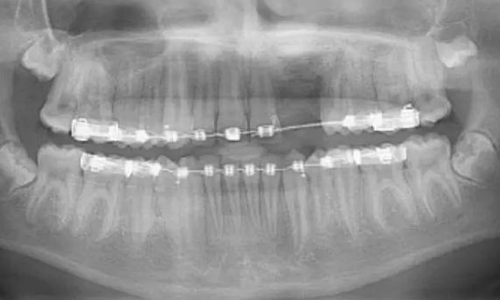

一名 23 區(qū)的9歲患者,在診所接受檢查時(shí)發(fā)現(xiàn)口內(nèi)中存在大范圍含牙囊腫[圖1]。由于上頜竇下沿出現(xiàn)大范圍突出,迫切需要接受囊腫去除手術(shù)[圖2和3]。

術(shù)前全景片[圖1]